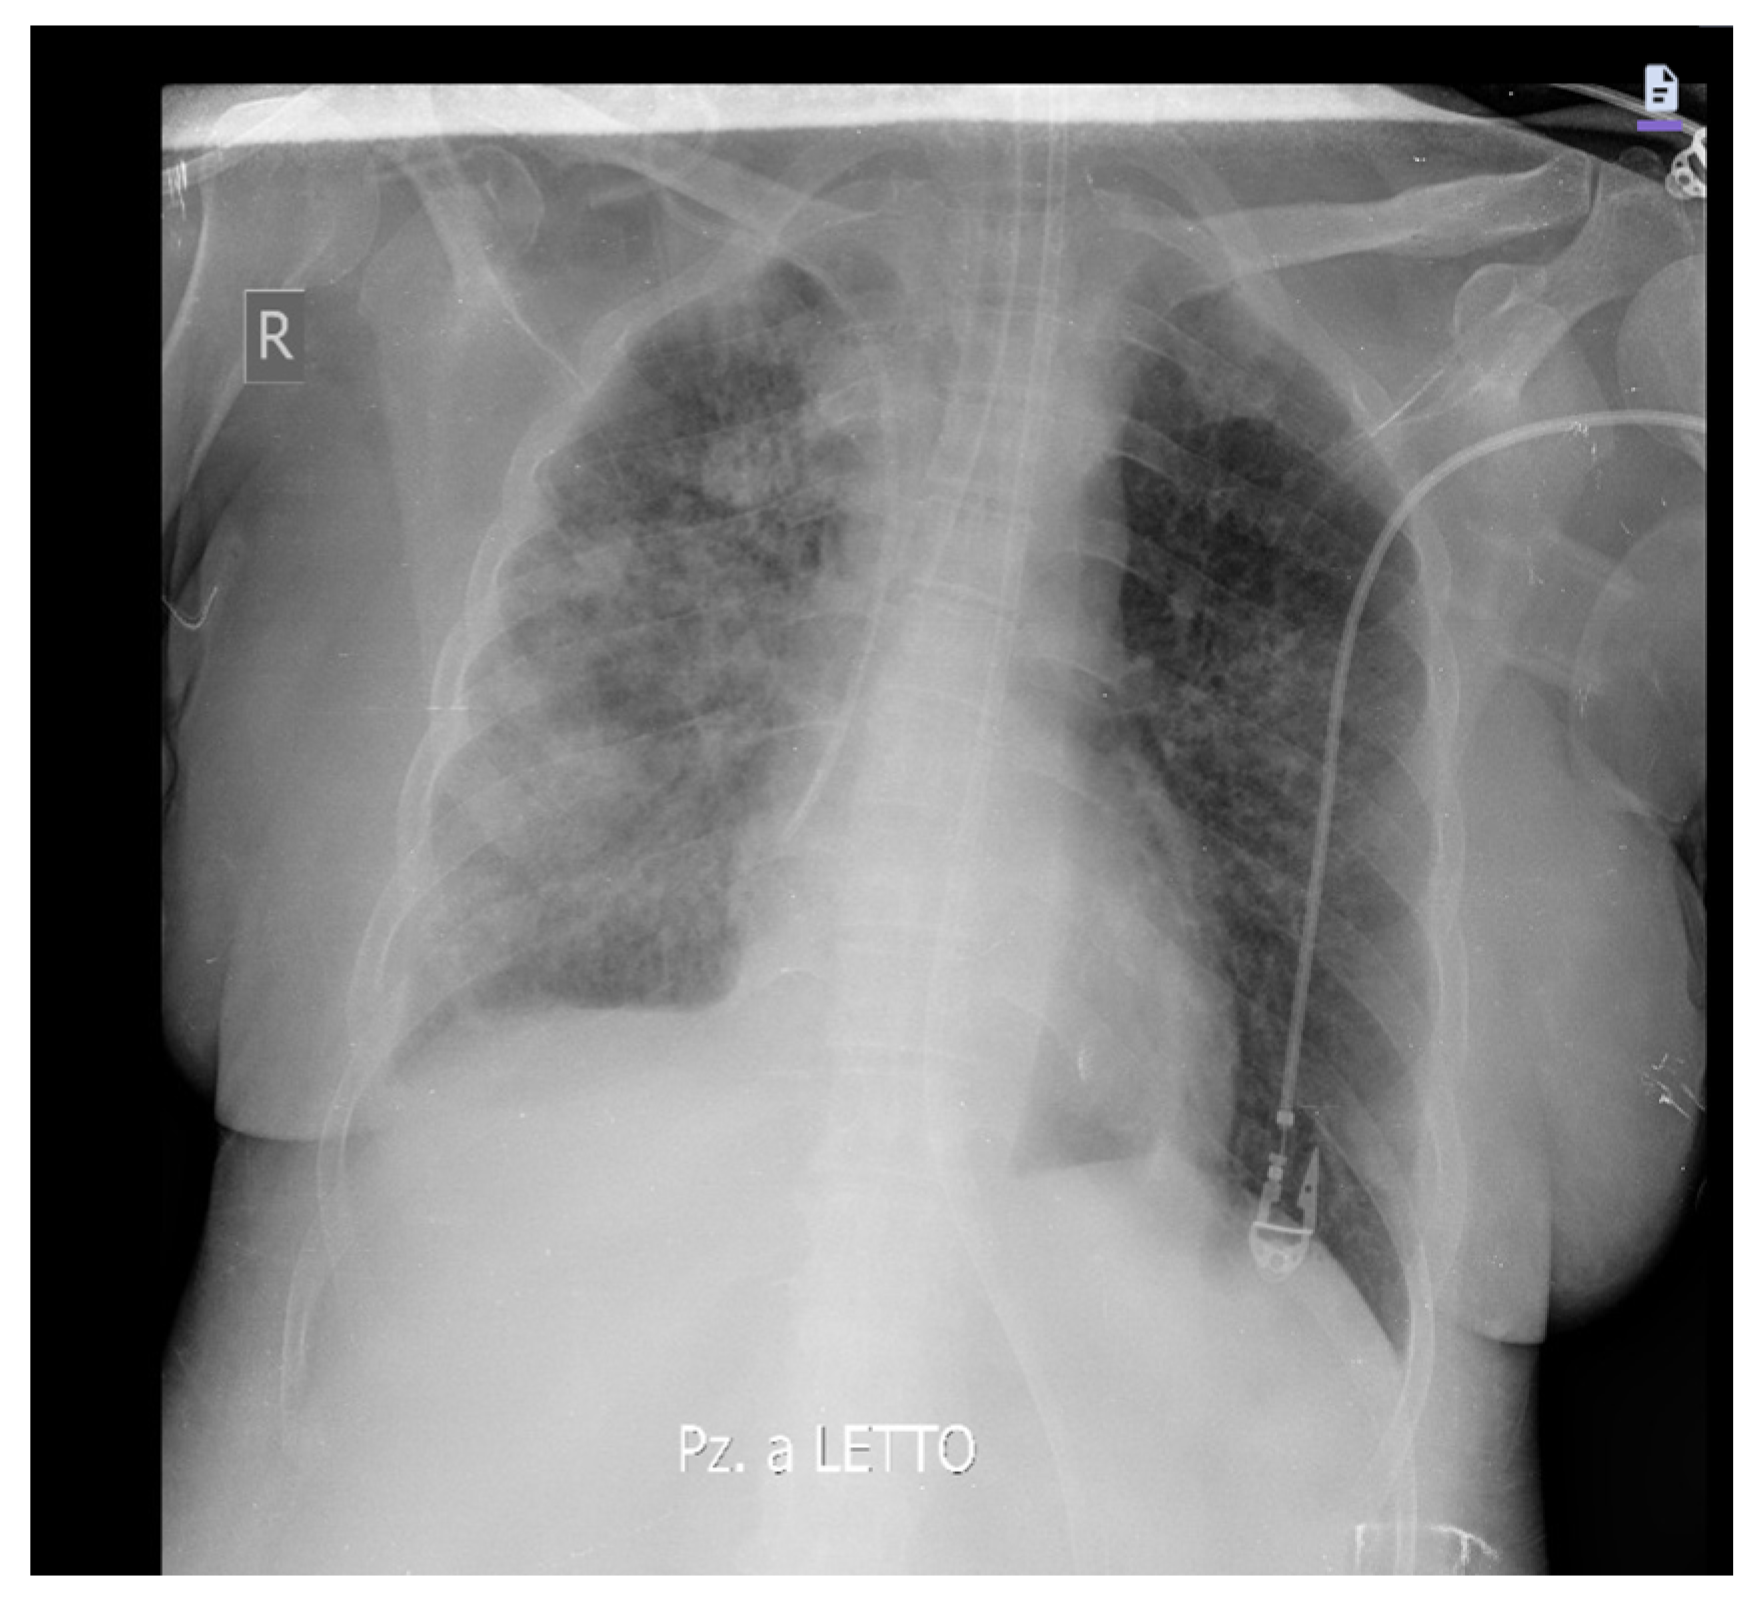

2. Case Presentation